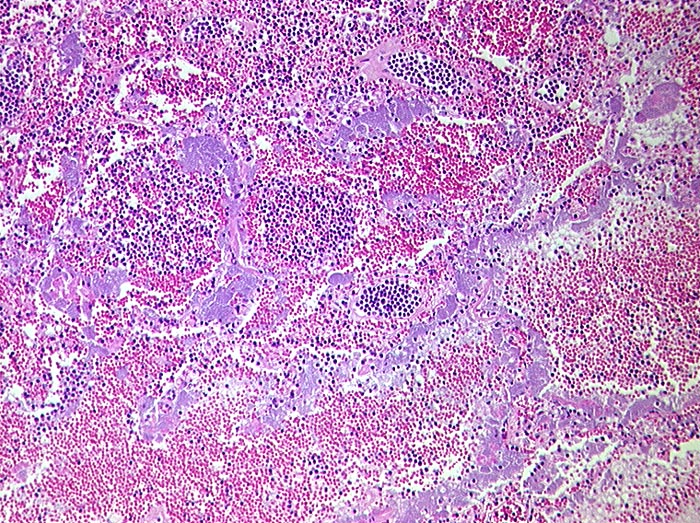

Areaktive Pneumonie

Entzündung infektiös

Lunge

Morphologie

Pathologischer Befund